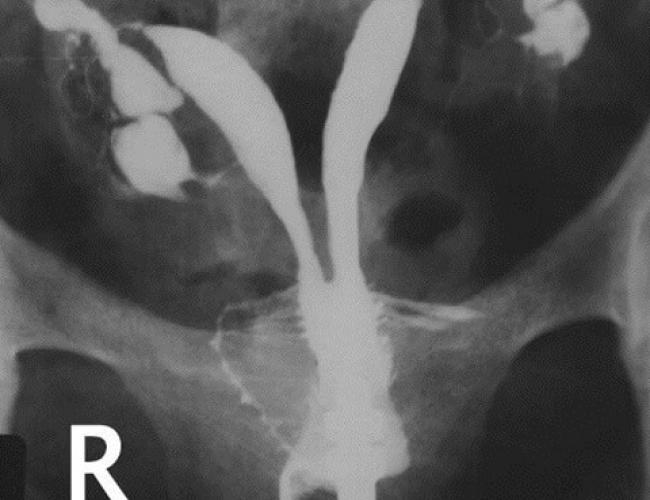

RAHİM FİLMİ

• Kadınlarda sağlı solu iki adet tüp bulunmaktadır. Tüplerle ilgili herhangi bir sorun tespit edilirse hastanın tüp bebek yaptırması gerekebilir.